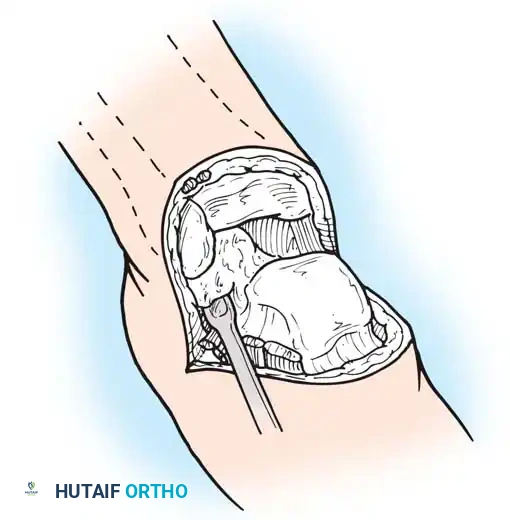

Step 3: Posterior Dissection and Calcanectomy

- Place a bone hook into the posterior aspect of the talus to provide forceful equinus traction. Proceed with posterior dissection, dividing the posterior capsule of the ankle joint.

- Identify the Achilles tendon. Divide it directly at its insertion on the calcaneus.

Pitfall: Do not damage the overlying posterior skin during Achilles tenotomy. Buttonholing the skin here will lead to necrosis of the entire heel flap.

- Using a periosteal elevator, dissect the soft tissues from the lateral and medial surfaces of the calcaneus. Pull the bone into extreme equinus.

- Continue subperiosteal dissection on the inferior surface of the calcaneus until the distal end of the plantar skin flap is reached. Remove the entire foot, leaving only the heel flap.